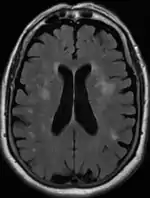

Axial T2 FLAIR sequence MR image of a middle-aged man with leukoaraiosis.

Leukoaraiosis is a particular abnormal change in appearance of white matter near the lateral ventricles. It is often seen in aged individuals, but sometimes in young adults.[1][2] On MRI, leukoaraiosis changes appear as white matter hyperintensities (WMHs) in T2 FLAIR images.[3][4] On CT scans, leukoaraiosis appears as hypodense periventricular white-matter lesions.[5]

The term "leukoaraiosis" was coined in 1986[6][7] by Hachinski, Potter, and Merskey as a descriptive term for rarefaction ("araiosis") of the white matter, showing up as decreased density on CT and increased signal intensity on T2/FLAIR sequences (white matter hyperintensities) performed as part of MRI brain scans.

These white matter changes are also commonly referred to as periventricular white matter disease, or white matter hyperintensities (WMH), due to their bright white appearance on T2 MRI scans. Many patients can have leukoaraiosis without any associated clinical abnormality. However, underlying vascular mechanisms are suspected to be the cause of the imaging findings. Hypertension, smoking, diabetes,[3] hyperhomocysteinemia, and heart diseases are all risk factors for leukoaraiosis.